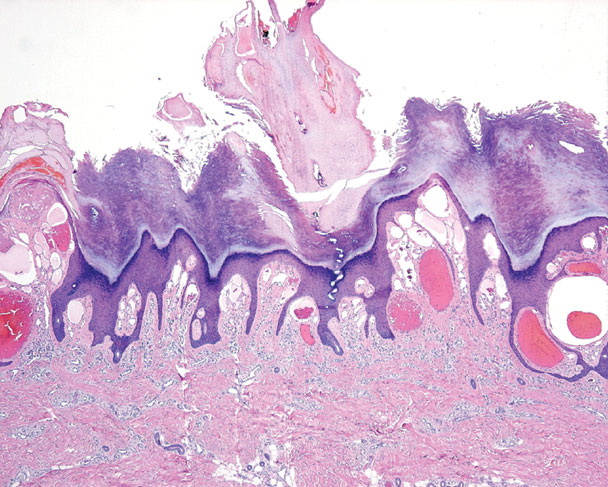

Verrucous hemangioma = الوعاؤوم الدموي المتثألل